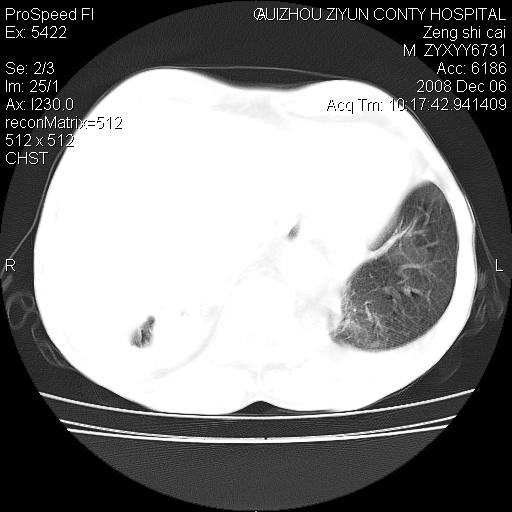

标题: CT16961:M、71岁,咳嗽半年,无血痰;胸片示右肺占位。 [打印本页]

标题: CT16961:M、71岁,咳嗽半年,无血痰;胸片示右肺占位。

右肺纵隔型肺癌伴纵隔淋巴结转移!双侧胸水!

1)考虑右肺上叶纵隔型肺癌伴纵隔淋巴结转移。2)心包积液,双侧胸腔积液。

右肺癌并纵隔淋巴转移,腹膜后转移可能性大,两侧胸腔积液

右肺上叶纵隔型肺癌伴纵隔淋巴结转移。心包积液,双侧胸腔积液。

右肺纵隔型肺癌伴纵隔淋巴结转移!双侧胸水\\心包积液